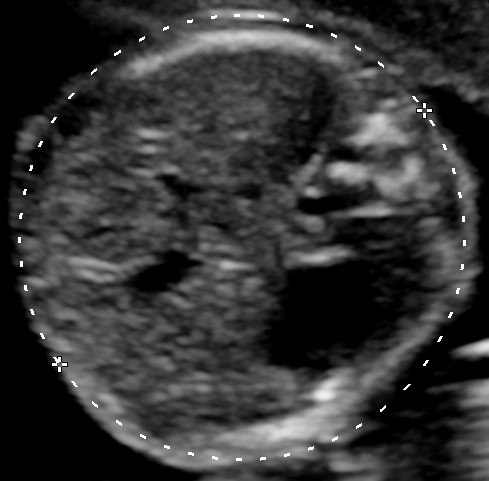

Measure the Fetal Head

fetal head biometry